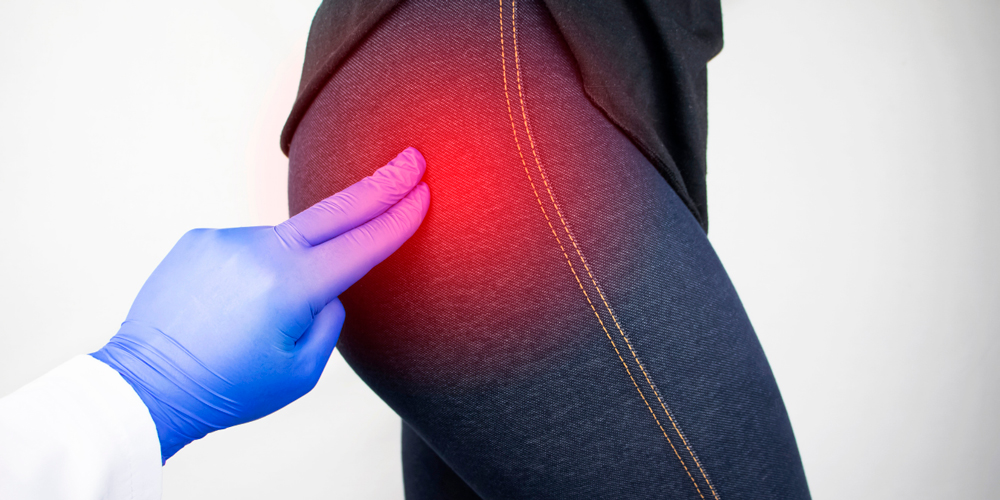

Боль в ягодице и бедре при сидении. Иногда ощущается сильный дискомфорт при сидении или лежании на определенном боку. Часто таким образом организм сигнализирует о вертельном бурсите.. Основным признаком этого заболевания является разная по интенсивности боль, локализованная в зоне поражения, левом или правом бедре и ягодице. Болезненность усиливается при ходьбе.